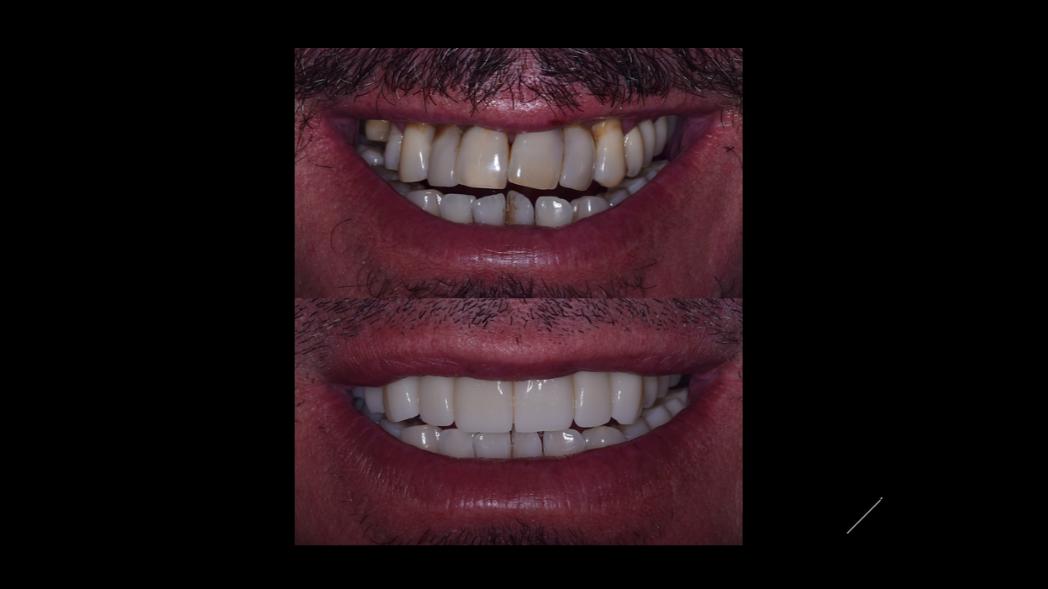

Περιστατικά Πριν - Μετά